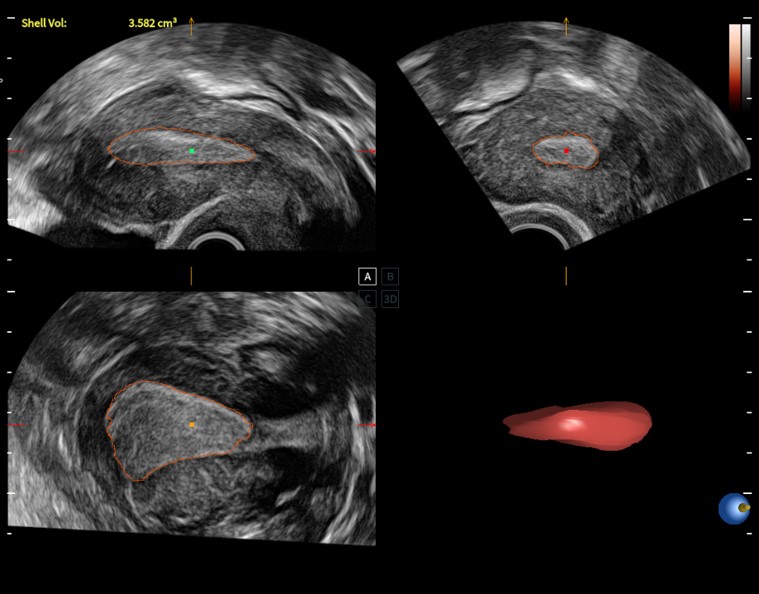

- FreeHand 3D – режим поверхностной трехмерной реконструкции

- Расчеты для акушерства, гинекологии, ангиологии, урологии, ортопедии, поверхностных, абдоминальных органов, кардиологии, головного мозга и сердца плода (в том числе STIC), вывода кривых роста плода, автоматический анализ толщины комплекса интима-медиа